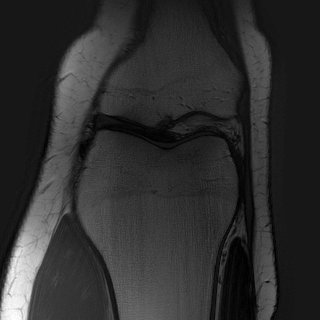

MRI with multi-contrast side information: We use fastMRI knee dataset (Zbontar et al., 2018) with the ContextMRI model (Chung et al., 2025). We pair PD and PDFS contrasts, reconstructing one from the other under undersampling with 2% ACS. We use normalized mutual information (NMI) as reward, which is robust to contrast changes. Fig. 6 highlights sharper edges and more faithful structure. Table 10 in Appendix D.3 shows our methods consistently improves the baseline in all the metrics of interest.

We used the contrast-pairings among the files in the fastMRI dataset, provided by (Atalık et al., 2025). We collect the data from the (fastMRI) source and preprocess to be compatible with the inputs in ContextMRI. Specifically, the setup used in the data is multi-coil MRI acquisition, which requires us to estimate the coil sensitivity maps, and then a complex reconstruction from them. ContextMRI takes complex values as inputs and denoises to produce a complex-valued 2D image. We computed NMI with bins at each step of the diffusion process to balance complexity with performance. We use the defaults parameters as in ContextMRI, except for the acceleration factor, and the center fraction (ACS), . We use a pair of anatomy which two contrasts, which has more 30 slices. We consider the slices to as these are more challenging and report the results by using one as the side information for the other.

| PDFS with PD | ||||

|---|---|---|---|---|

| Algorithm | PSNR () | SSIM () | LPIPS () | NMI () |

| RFJS | 25.85 | 0.801 | 0.375 | 0.457 |

| GS | 25.33 | 0.797 | 0.375 | 0.455 |

| BON | 25.47 | 0.797 | 0.376 | 0.454 |

| ContextMRI | 25.39 | 0.795 | 0.383 | 0.451 |

| PD with PDFS | ||||

| RFJS | 27.85 | 0.920 | 0.358 | 0.579 |

| GS | 27.80 | 0.920 | 0.360 | 0.579 |

| BON | 27.80 | 0.918 | 0.366 | 0.570 |

| ContextMRI | 27.46 | 0.915 | 0.375 | 0.563 |